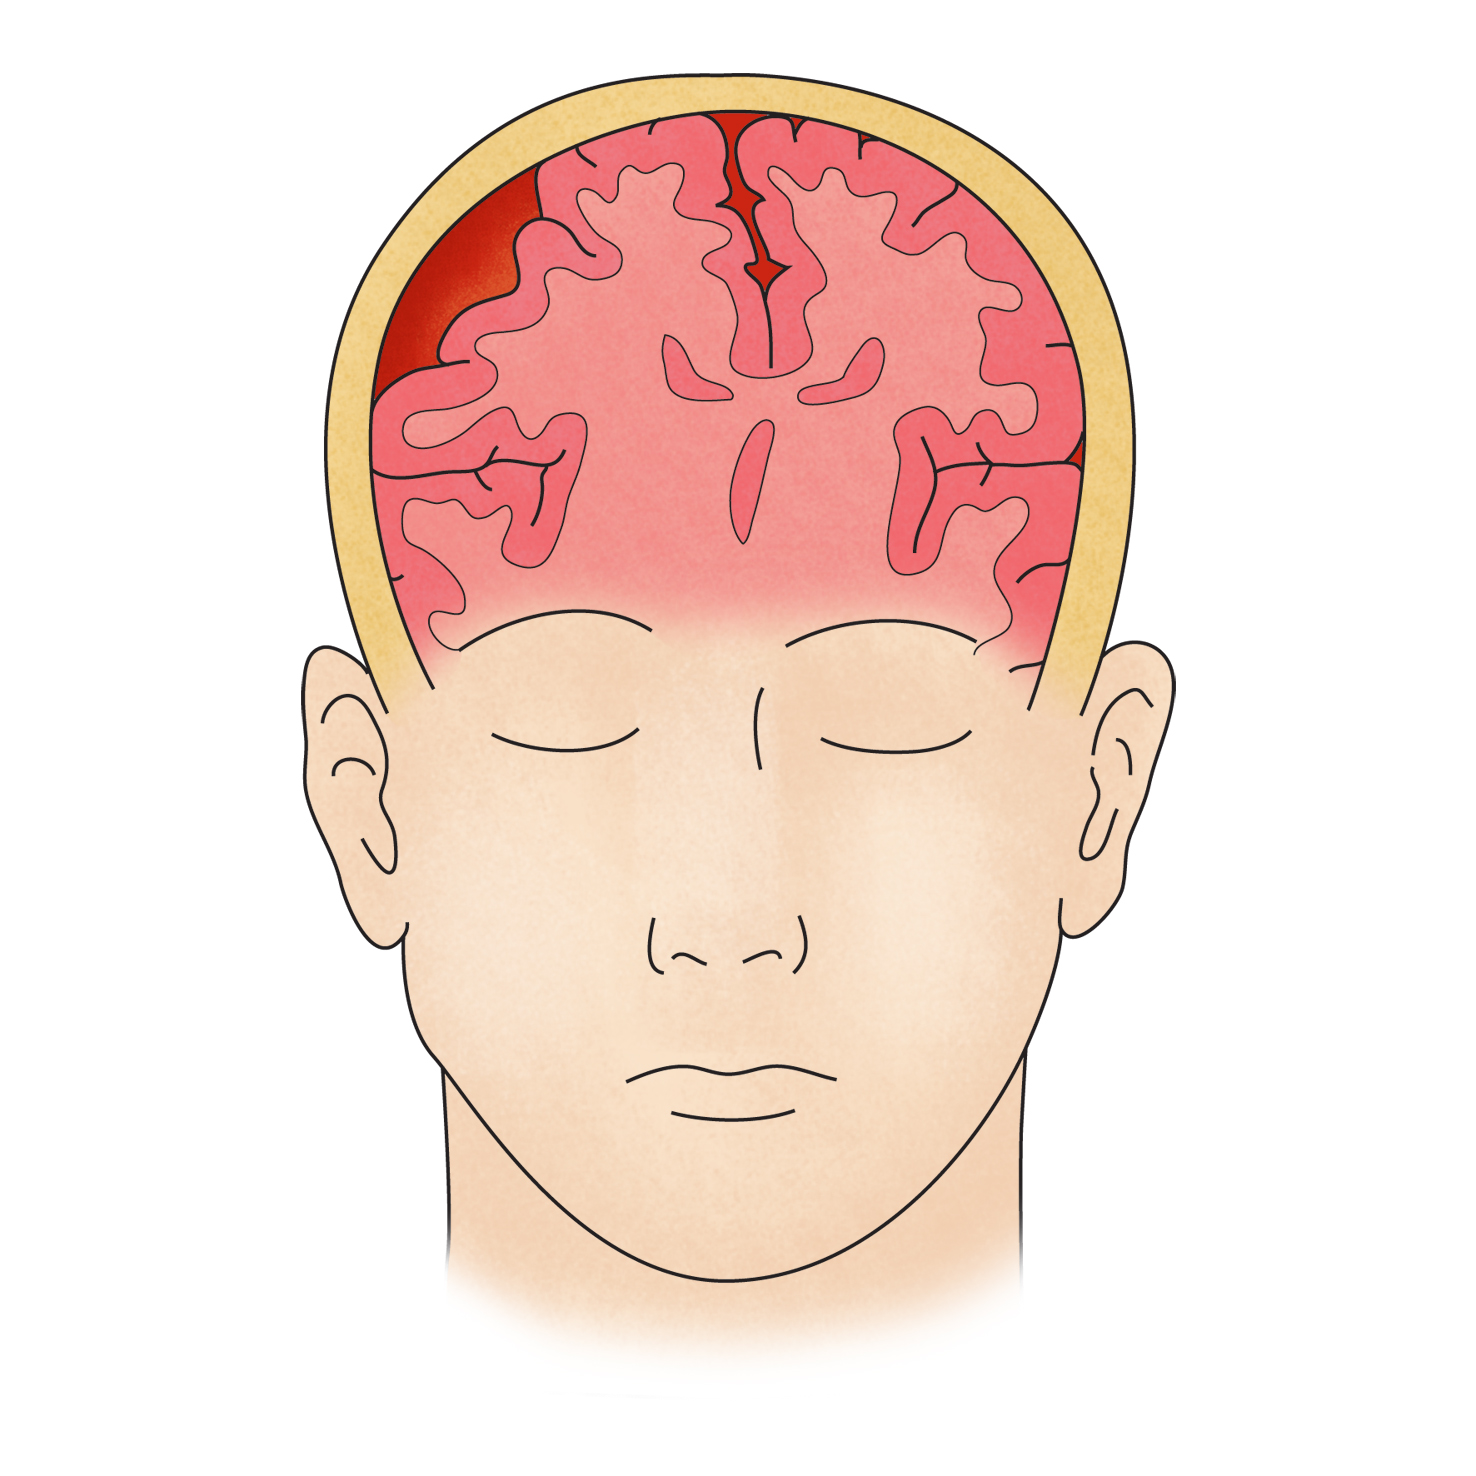

자발성 두개강 내 출혈(Spontaneous intracranial hemorrhage)

자발성 두개강 내 출혈은 뇌의 안쪽에 있는 가느다란 혈관이 터져서 뇌 속에 피가 고이고, 이로 인해 뇌가 손상되는 것을 말합니다. 이것은 대부분 고혈압이 조절되지 않을 때 발생합니다. 고혈압이 오래되면 비교적 작은 직경의 뇌혈관 벽을 손상시켜서 혈압 증가 시 혈압이 터져 버립니다. 뇌 내 출혈은 뇌출혈의 가장 흔한 형태이기 때문에 말 그대로 '뇌출혈'이라고도 부릅니다.

환자는 어지럽거나, 머리가 아픈 증상을 호소하며, 그 후에는 잘 토합니다. 그와 동시에 몸의 반신이 말을 잘 듣지 않습니다. 또한 갑작스러운 의식 변화, 두통, 혈압 상승, 반신 편마비 등이 나타나기도 합니다.